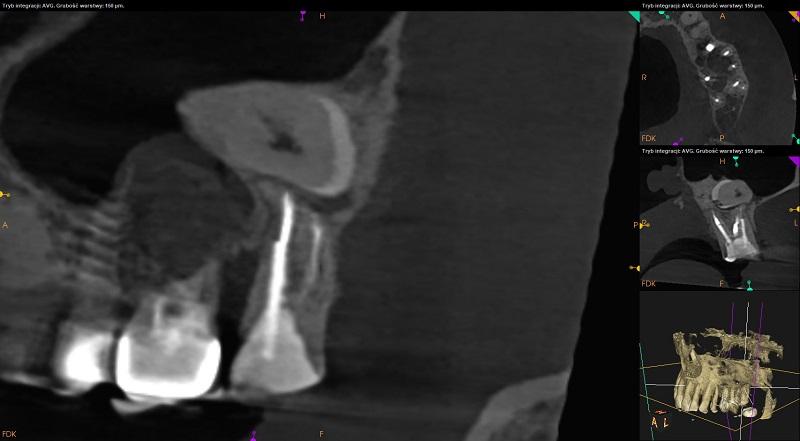

Tomografia szczęka.

Rozrost błony śluzowej w zachyłku zębodołowym i na ścianie

przyśrodkowej w zatoce prawej (do 5mm) oraz w zachyłku zębodołowym

w zatoce lewej (do 3,5mm).

Ciągłość blaszki kortykalnej dna zatok szczękowych przerwana w

okolicach wierzchołków korzeni zębów 17,16 po stronie prawej, 24

oraz okolicy 25,26,27 po stronie lewej.

Widoczny uogólniony zanik wysokości tkanki kostnej wyrostka zębodołowego szczęki (ubytek kości około 4mm) oraz ścieńczenie blaszki zbitej po stronie przedsionkowej przy zębach 13,12,11,21,24.

Ząb 17 – przeleczony kanałowo. Odbudowany protetycznie koroną na wkładach. W części przywierzchołkowej kanałów materiał wypełniający niewidoczny (kanał dystalny – 1mm, podniebienny - 1mm). Widoczne cztery światła kanałów. Kanał dodatkowy (MB2) niewypełniony.

Wokół wierzchołka korzenia mezjalnego ognisko rozrzedzenia struktury kostnej o charakterze torbieli (5,5mm x 5mm x 3mm).

Szpara ozębnej wokół wierzchołka korzenia dystalnego poszerzona.

Ząb 16 – bez znamion leczenia kanałowego. Widoczne cztery światła kanałów. Szpara ozębnej wokół wierzchołka korzenia dystalnego poszerzona.

Brak zęba 25 uzupełniony implantologicznie. Struktura tkanki kostnej po stronie mezjalnej przedsionkowej i podniebiennej śruby implantologicznej radiologicznie prawidłowa.

Ząb 26 – przeleczony kanałowo. Odbudowany protetycznie koroną na wkładach. Cztery kanały wypełnione na całej swojej długości z nadmiarem. W korzeniu dystalnym perforacja ściany w okolicy bifurkacji – rozległa zmiana o charakterze torbieli wokół korzenia (9,5mm x 8,5mm x 8,5mm).

Zmiana dochodzi do ściany dystalnej śruby implantologicznej.

Ząb 27 - po leczeniu kanałowym. W części przywierzchołkowej kanału mezjalnego materiał wypełniający niewidoczny (2,5mm). Wierzchołek korzenia mezjalnego zaięty, widoczna transportacja światła kanału. Tkanki okołowierzchołkowe bez widocznych radiologicznie cech patologicznych.

Pozostałe zęby bez znamion leczenia kanałowego. Tkanki okołowierzchołkowe bez widocznych radiologicznie cech patologicznych.

Ząb 28 – zatrzymany. Położony poziomo nad wierzchołkami korzeni zęba 27, koroną skierowny w stronę dystalną. Korzenie zęba 28 w świetle zatoki szczękowej lewej. Wokół korony zęba 28 dobrze odgraniczony jednokomorowy ubytek struktury kostnej z uwapnionymi złogami wewnątrz (13,5mm x 10,5mm x 16,5mm). Zmiana obejmuje blaszkę zbitą po stronie przedsionkowej i podniebiennej oraz wpukla się do światła zatoki szczękowej. Obraz radiologiczny może odpowiadać włókniakozębiniakowi szkliwiakowemu (AFD) – do konsultacji chirurga szczękowo-twarzowego.

Radiologiczne przejaśnienia mogące odpowiadać próchnicy lub ubytkom w zębach: 18 – strona mezjalna, 16 – strona dystalna 15 – strona mezjalna i dystalna poniżej wypełnienia - do dalszej diagnostyki klinicznej.